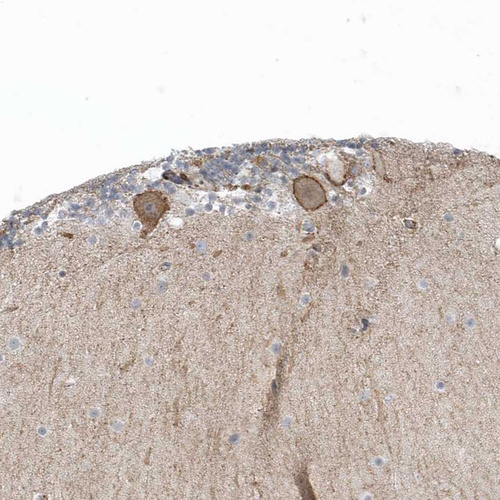

Immunohistochemistry analysis in human cerebral cortex and skeletal muscle tissues using HPA035326 antibody. Corresponding CACNB2 RNA-seq data are presented for the same tissues.